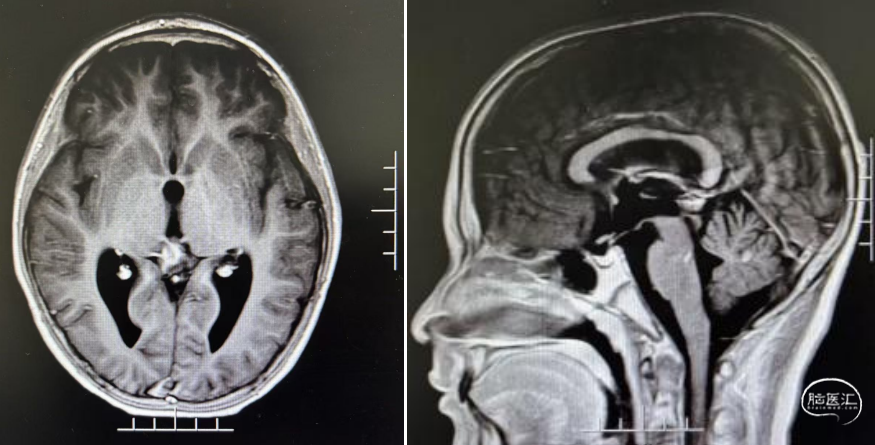

实验室检查:甲胎蛋白(AFP):3.535ng/ml,参考范围(0-10);人绒毛膜促性腺激素(β-HCG):163.0mIU/MI,参考范围(0-2)。

经儿童脑肿瘤MDT讨论后,考虑生殖细胞肿瘤,建议先化疗再放射治疗。1疗程后病变明显退缩。结疗后复查,肿瘤基本消失。此后3年予以定期复查未见复发。

结疗3年后随访